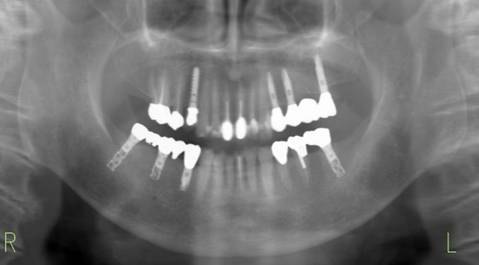

治療後。歯周病で失われた骨が回復しています。使用インプラントはスプラインツイストです。

上部構造装着後6年。ハイブリッドレジンを使用したため、少し艶がなくなってきました。上部構造の材料には金属、ハイブリッドレジン、セラミックなどがあります。セラミックはきれいですが欠けやすいため、最近はフルジルコニアを使っています。

インプラント装着後6年。順調に経過しています。12か月毎のメインテナンスをしています。